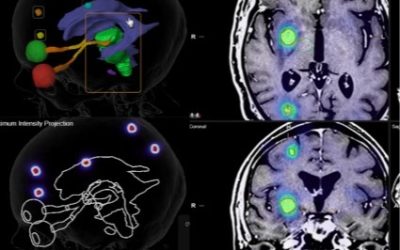

La radiocirugía craneal (SRS) y extracraneal (SBRT), parte III. Alcance

¿Hasta dónde llegan la radiocirugía craneal y extracraneal (SRS y SBRT)? Ambos tratamientos se diseñan como un “traje a medida” de las metástasis a tratar. Gracias a las pruebas de imagen como el...